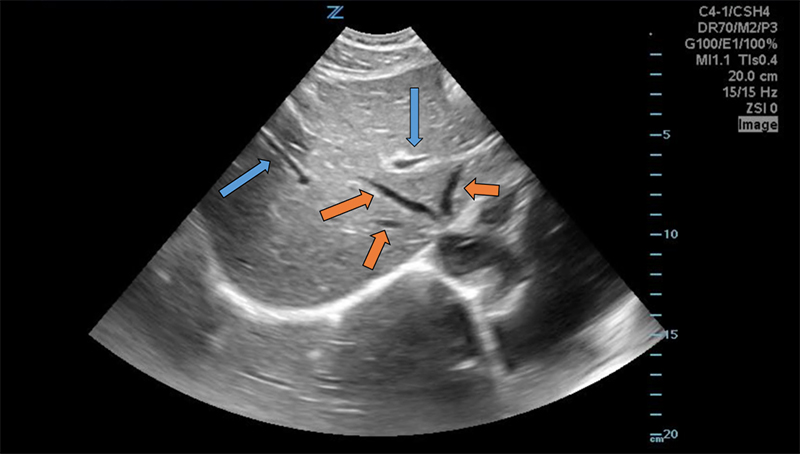

- The portal vein may also be located in short axis by tracing the gallbladder down its long axis to the neck, forming the “exclamation point”

Figure 9. “Exclamation point” revealing the gallbladder (GB) in long axis with the bright-walled portal vein (PV) in short axis.

- The larger, bright-walled portal vein will often be seen with the two smaller structures of the portal triad in the same cross section, a hepatic arterial branch and common bile duct.

Figure 10. The portal triad seen in short axis. The portal vein (PV) is the largest, while the hepatic artery and bile duct (arrows) are much smaller and often indistinguishable without color Doppler.